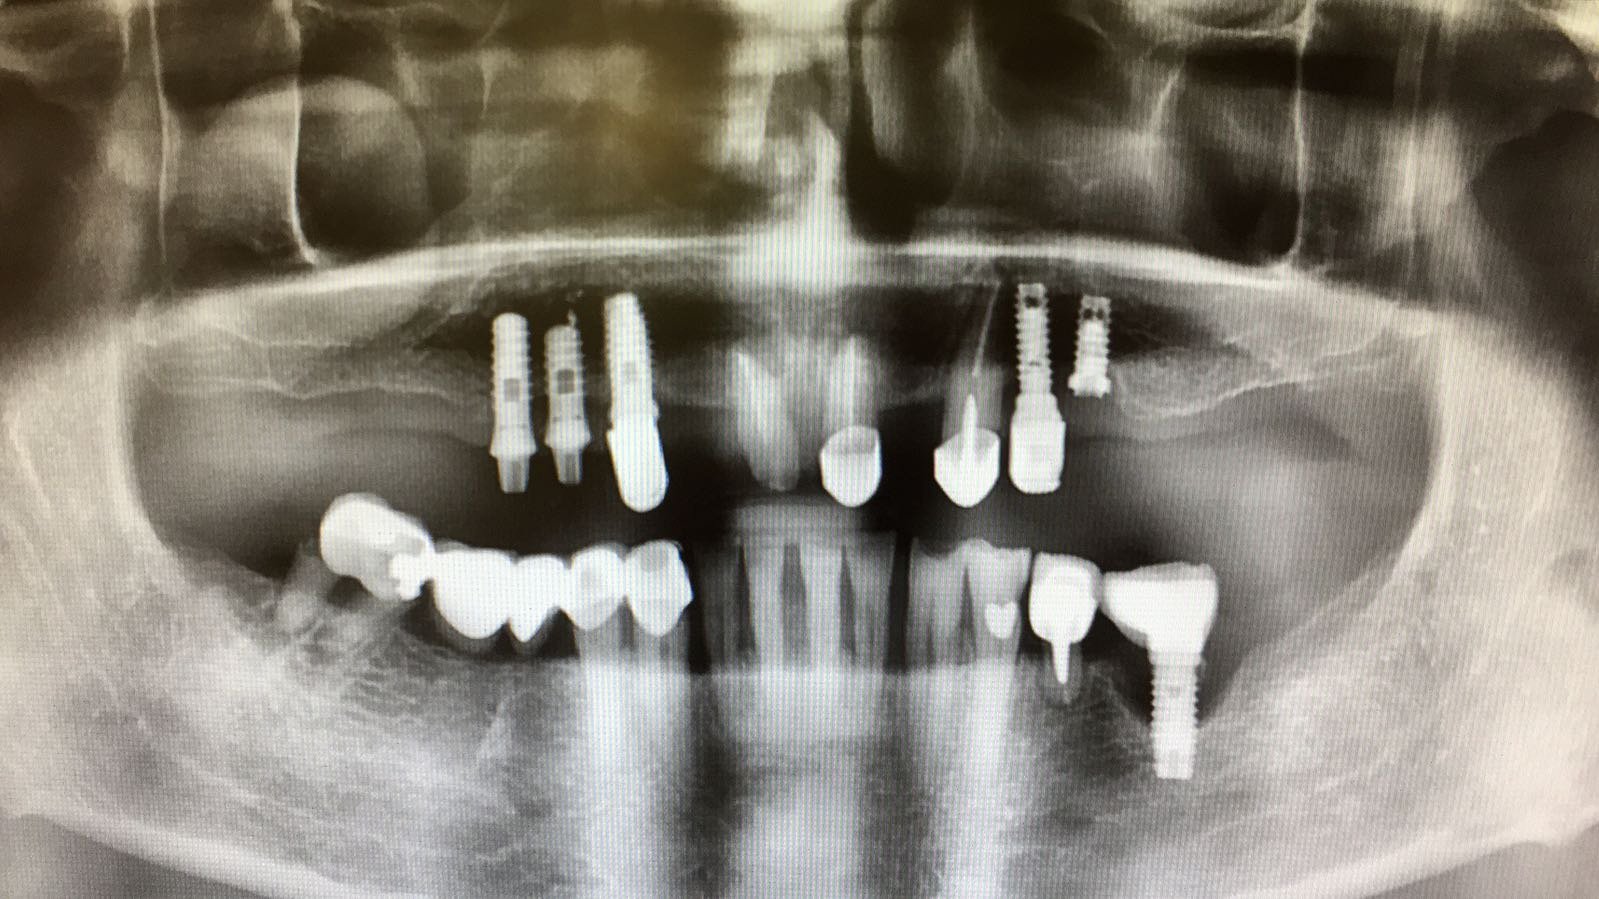

Paciente que ha sido tratada anteriormente en 2 consultas. En la primera le colocaron implantes Astra y después de 3 años cargados, 2 de ellos fracasaron por periimplantitis. En la [...]

Buenos días compañer@s! Me llega a la clínica este caso... tengo que rehabilitarlo, me podríais ayudar a identificar los implantes? Muchas gracias de antemano!!!!!!!!!